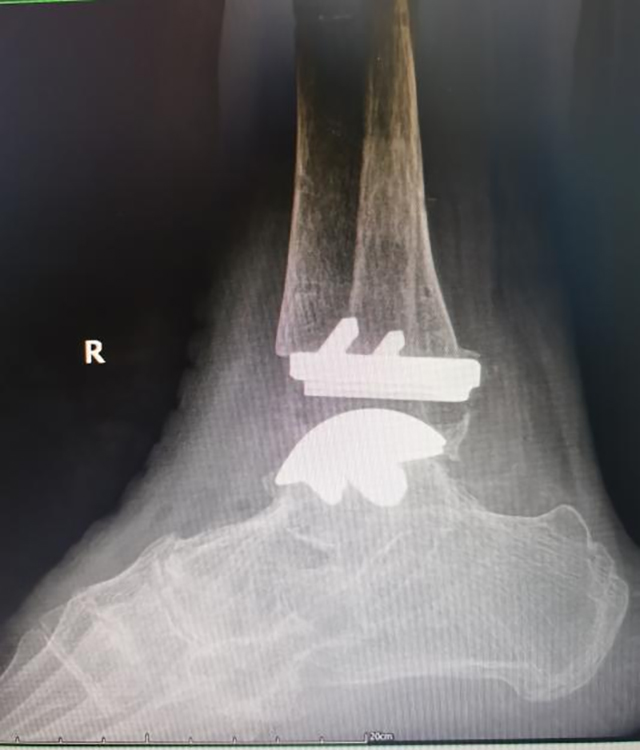

2023年3月26日,西南医科大学附属中医医院成功开展川南首例全踝关节置换术。目前,患者已痊愈出院。此次手术由医院副院长汪国友教授、大骨科主任兼骨伤科关节·足踝组主任扶世杰教授、骨伤科关节·足踝组张磊博士等骨伤科关节·足踝组手术团队实施。

完善充分的术前准备后,在麻醉科、放射影像科等多科室的通力配合下,骨伤科关节·足踝组手术团队按术前计划,精准手术,顺利完成了川南首例全踝关节置换术。

术中及术后复查显示踝关节假体力线良好,大小合适;

术前

术中

术后